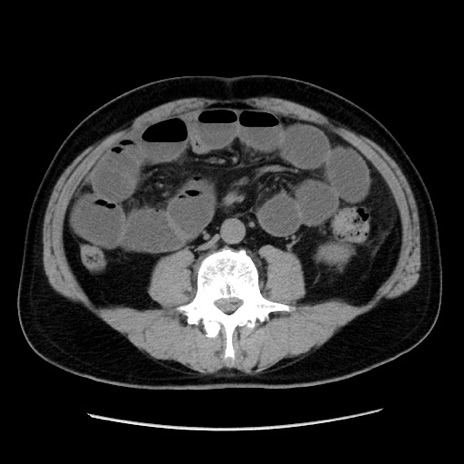

症例16(横断像)

【症例】 70歳代男性

【主訴】 腹痛、嘔吐

【現病歴】 約1ヶ月前より間欠的に腹痛と嘔吐あり、当院消化器内科を受診したところCTで多発する肝臓のLDAを指摘され、精査中であった。以降は消化器症状は安定していたが、2日前より嘔気と腹痛があり、同日より排便・排ガスが消失した。改善認めず、 本日、救急外来を受診した。

【既往歴】 大腸ポリープ切除後。

【身体所見】意識清明・会話良好、BT 36.3℃、BP 127/80mmHg、 P 80bpm、腹部:膨満あり、平坦・軟、上腹部正中および下腹部正中に圧痛あり、反跳痛なし、筋性防御なし。

【データ】WBC 7200、CRP 0.77